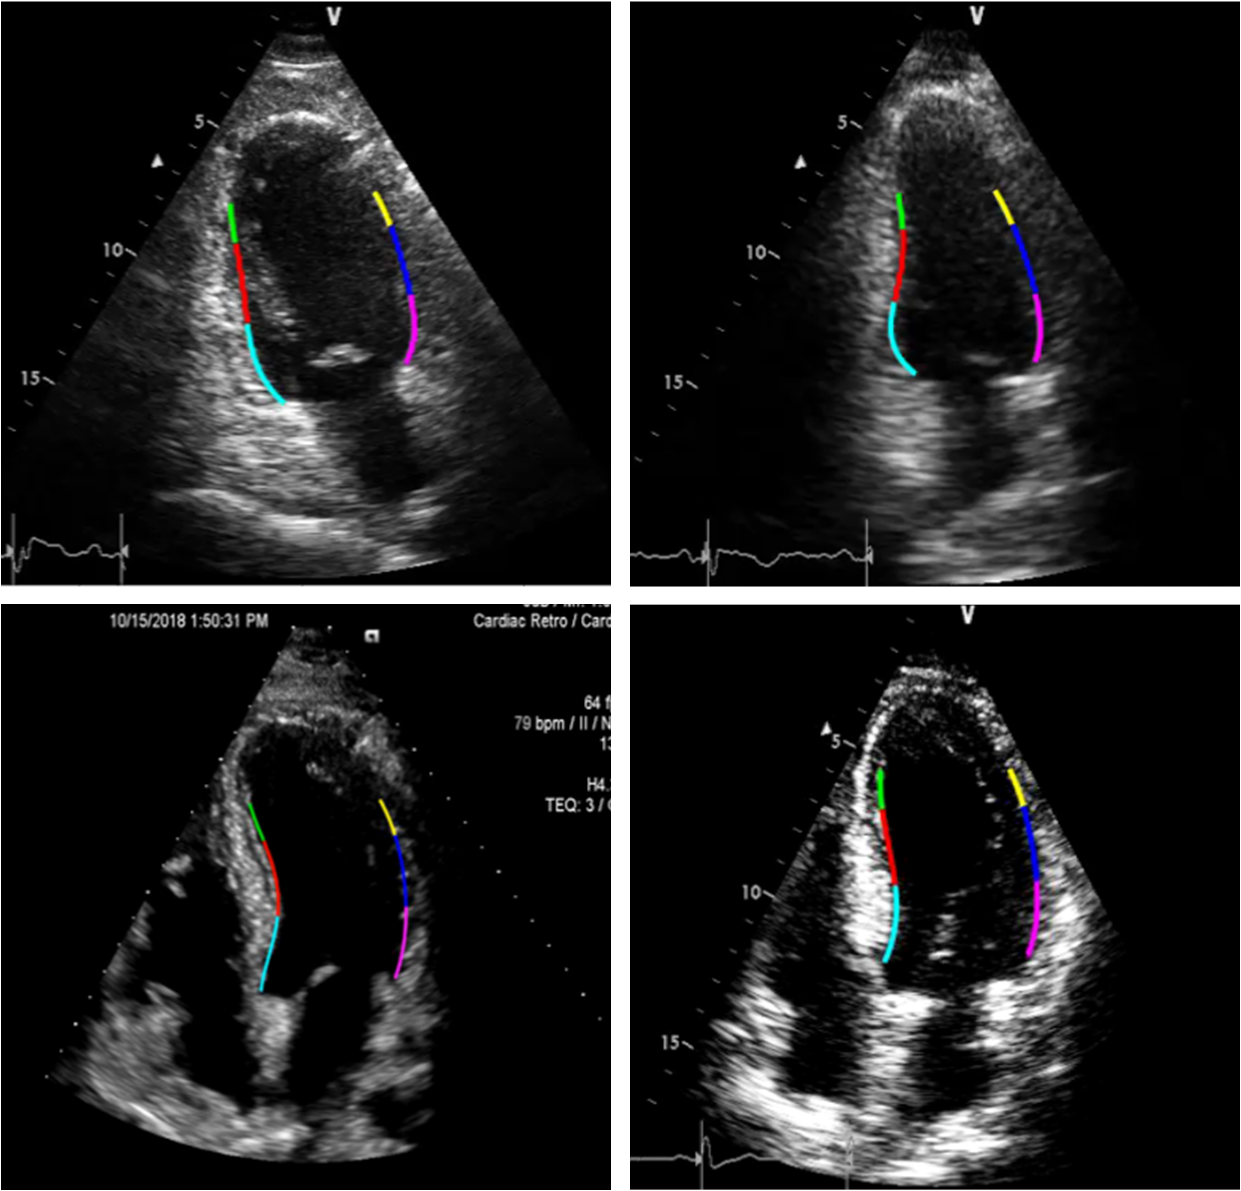

Refer to caption

Figure 9: A4C and A2C view frames for the endocardial boundary extraction process by the APs method. The sample images at the first row are subjected to artifacts, noise, or low contrast.

In Fig. 9, some examples of the APs formation can be depicted. The figure reveals that the APs can successfully represent the true endocardial boundary even for low quality A4C and A2C views.